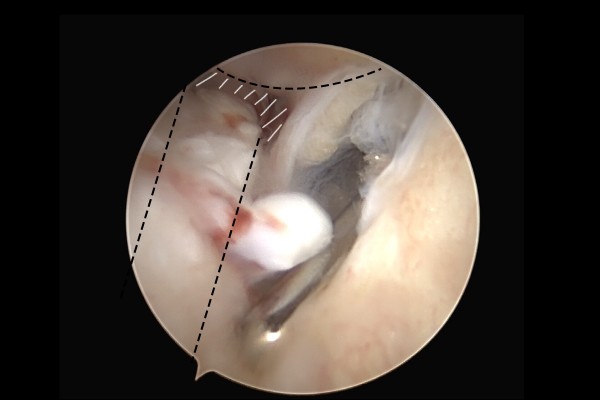

내시경 사진을 보시면 인대가 파열되어 끊어져서 뼈(바깥쪽 복숭아뼈, 비골)에 붙어있지 못 하고 틈이 보이는 것이 확인됩니다.